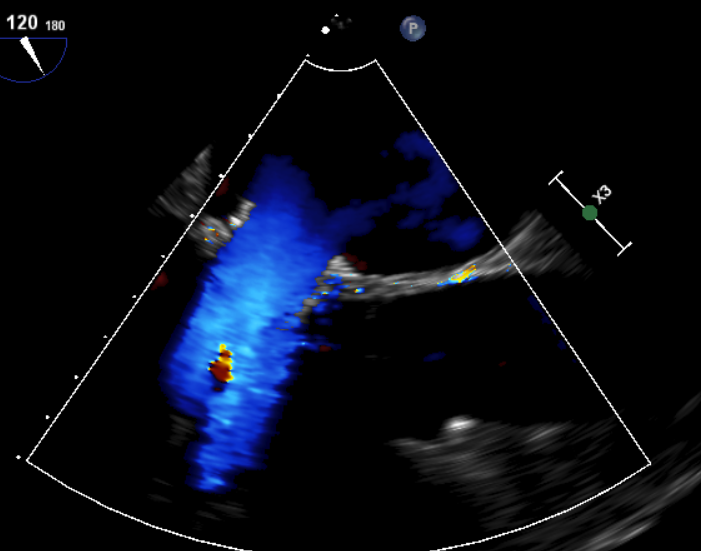

原生物瓣少量反流

过瓣流增快,呈“五彩状”

CDFI提示过瓣血流通畅

CDFI示少量瓣周漏

收缩期未见瓣周漏